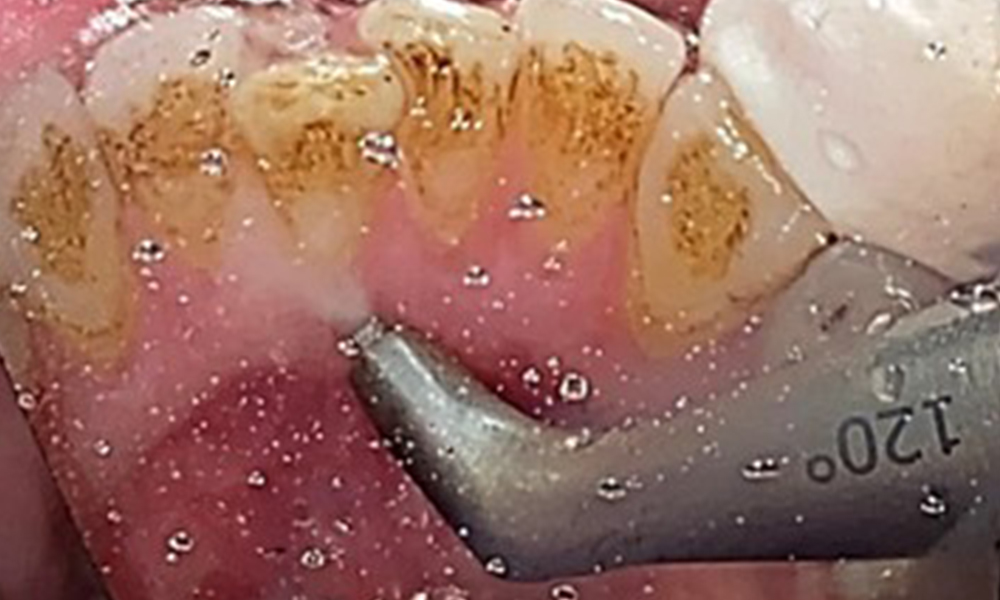

The objective would be to control disease risk by removing supragingival and subgingival biofilm. The instruments can be selected based on patient needs. First, calculus and any concretions must be removed using ultrasonic and/or manual instruments (Fig. 10).

Discolouration caused by nicotine and tea consumption can be removed easily using an air polisher (Fig. 11).

When using more abrasive powder, it is essential to work from a cervical to coronal direction and never point the outlet nozzle towards the gingiva to prevent potential emphysema. Good suction on the contralateral side is essential to reduce aerosol formation (Fig. 12).